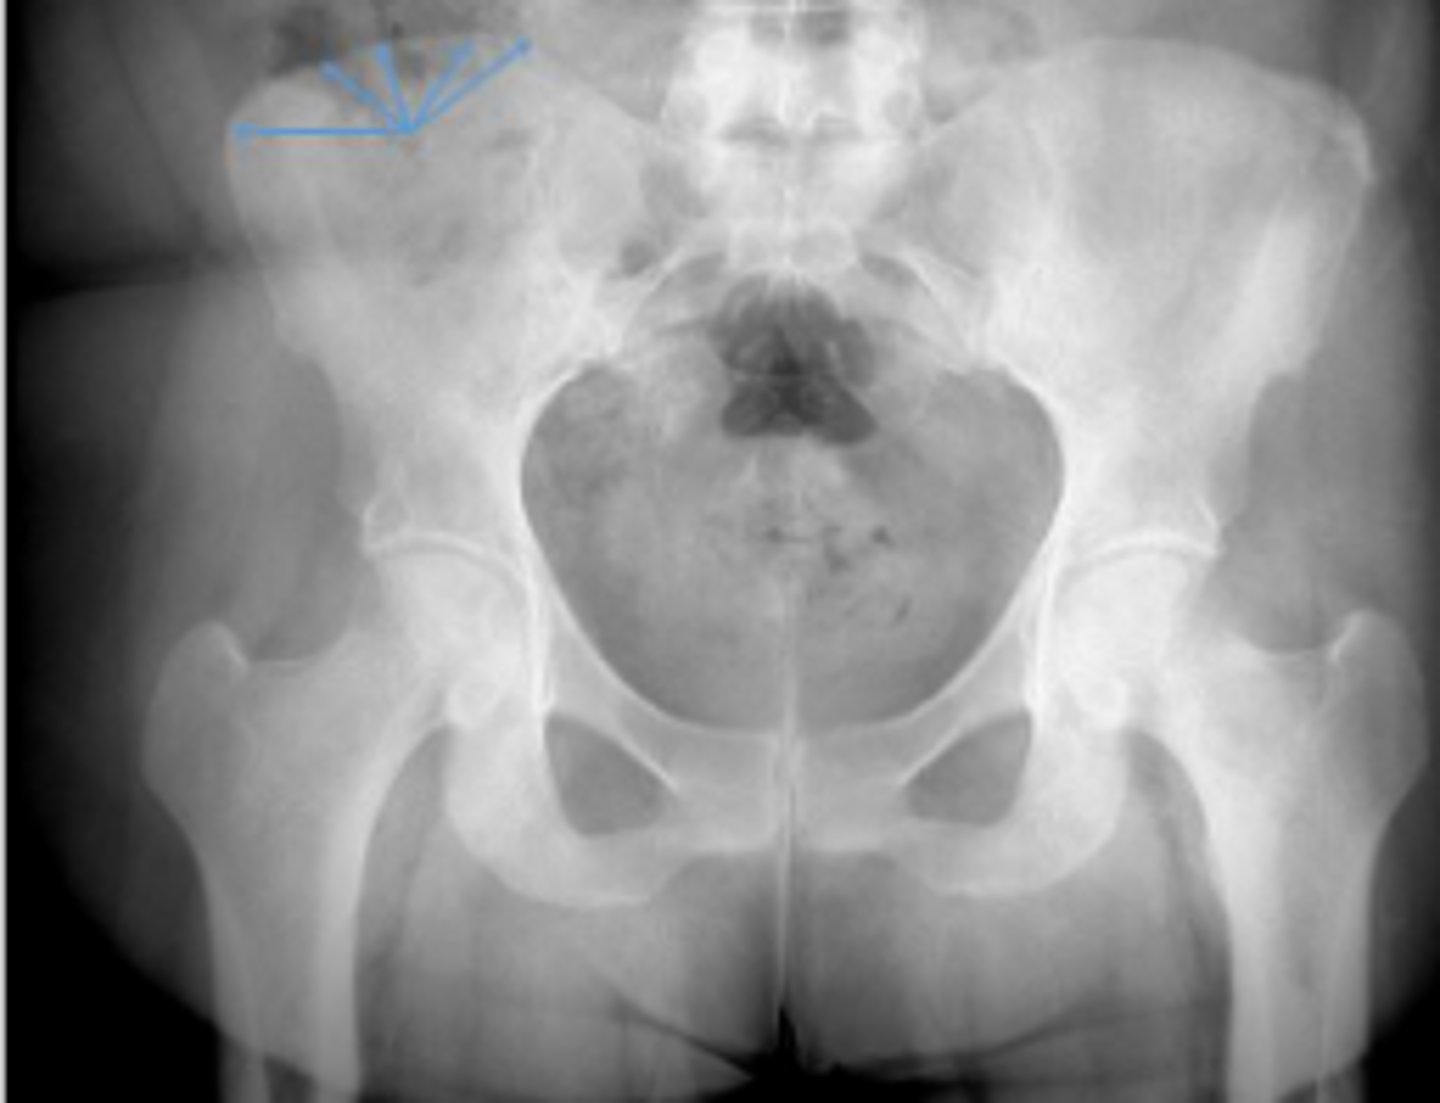

Bilateral frog leg view

What is the name of the radiographic view?

Phleboliths

What are the arrows pointing to?